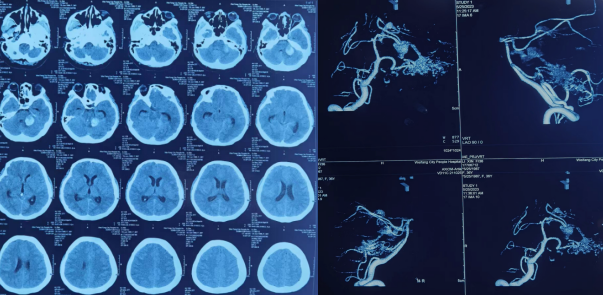

到达神经外三科后,科主任王玉亭组织疑难病例讨论,制定治疗计划,行脑血管造影(DSA)检查,诊断为颅内巨大动静脉漏合并蛛网膜下腔出血。蛛网膜下腔出血是妊娠期少见且严重的并发症,孕妇及胎儿的死亡率较高,以动脉瘤最多见,而脑动静脉瘘极少见。考虑患者刚刚分娩,较为虚弱,决定行脑动静脉瘘微创介入栓塞术。